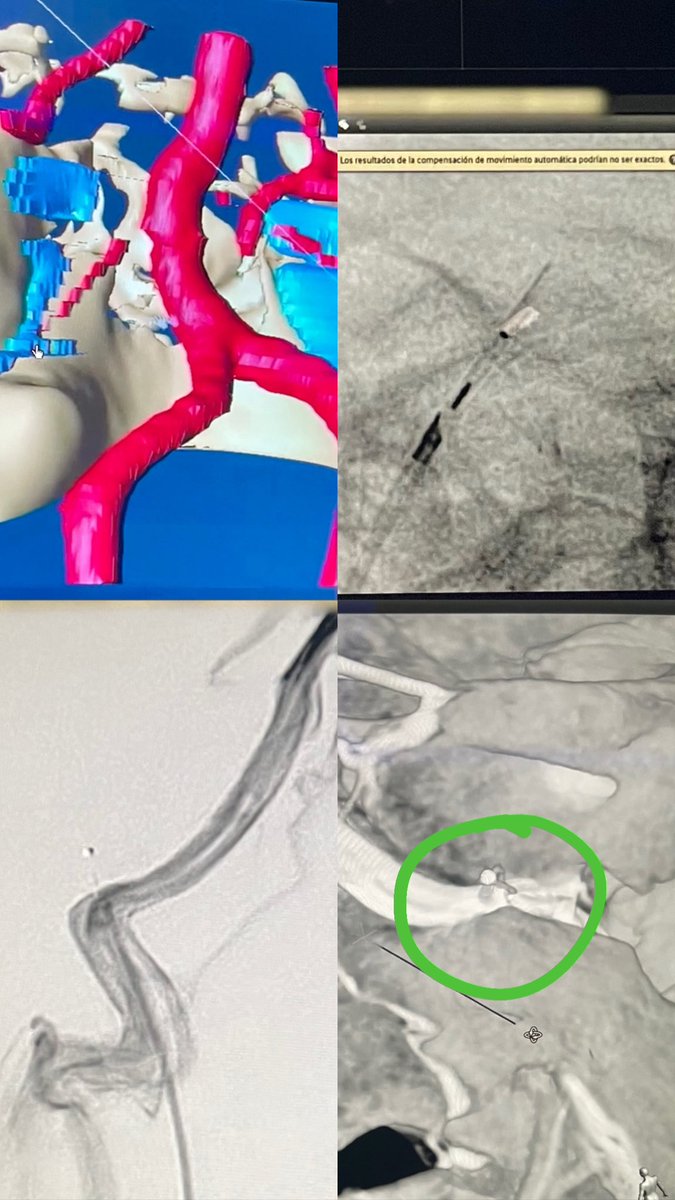

Case of the day. Fetal PcomA aneurysm. Endovascular treatment, jailing with Contour intrasacular device + coils. #neuroradiology #endovascular #aneurysm #embolization #intrasacular

1

5

24